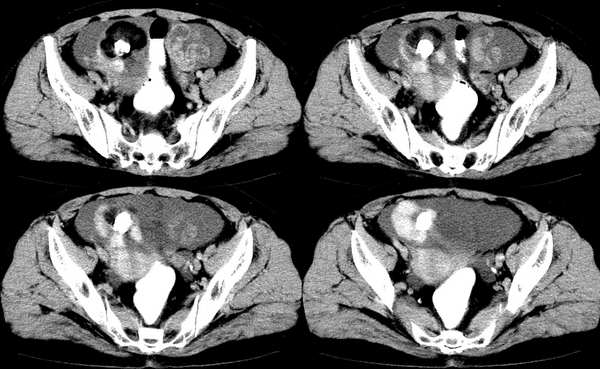

女,59岁,憋气、下腹不适一个月。胸透:双侧大量胸腔积液,反复抽胸水化验为漏出液。彩超示:盆腔占位

右侧卵巢区囊实性占位性病变,内见高密度及囊性脂肪密度,实性部分强化明显,囊性部分未见强化,结合病史多考虑:右侧卵巢恶性畸胎瘤。

右侧卵巢区囊实性占位性病变,内见高密度及囊性脂肪密度。考虑:右侧卵巢恶性畸胎瘤。